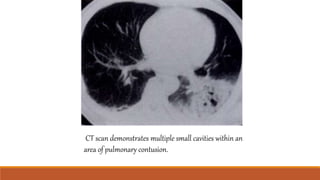

CT scan demonstrates multiple small cavities within an

area of pulmonary contusion.

CT scan demonstratesmultiple small cavities within an area of pulmonary contusion.